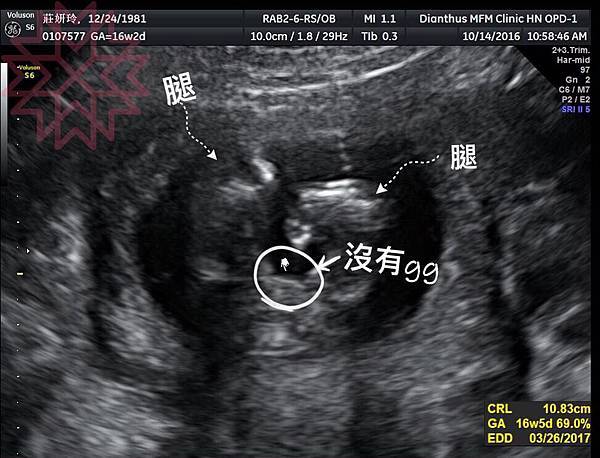

於是日子默默來到了16周產檢

醫生突然說:可以看到性別囉

登愣!!!蛋包是個女生啊